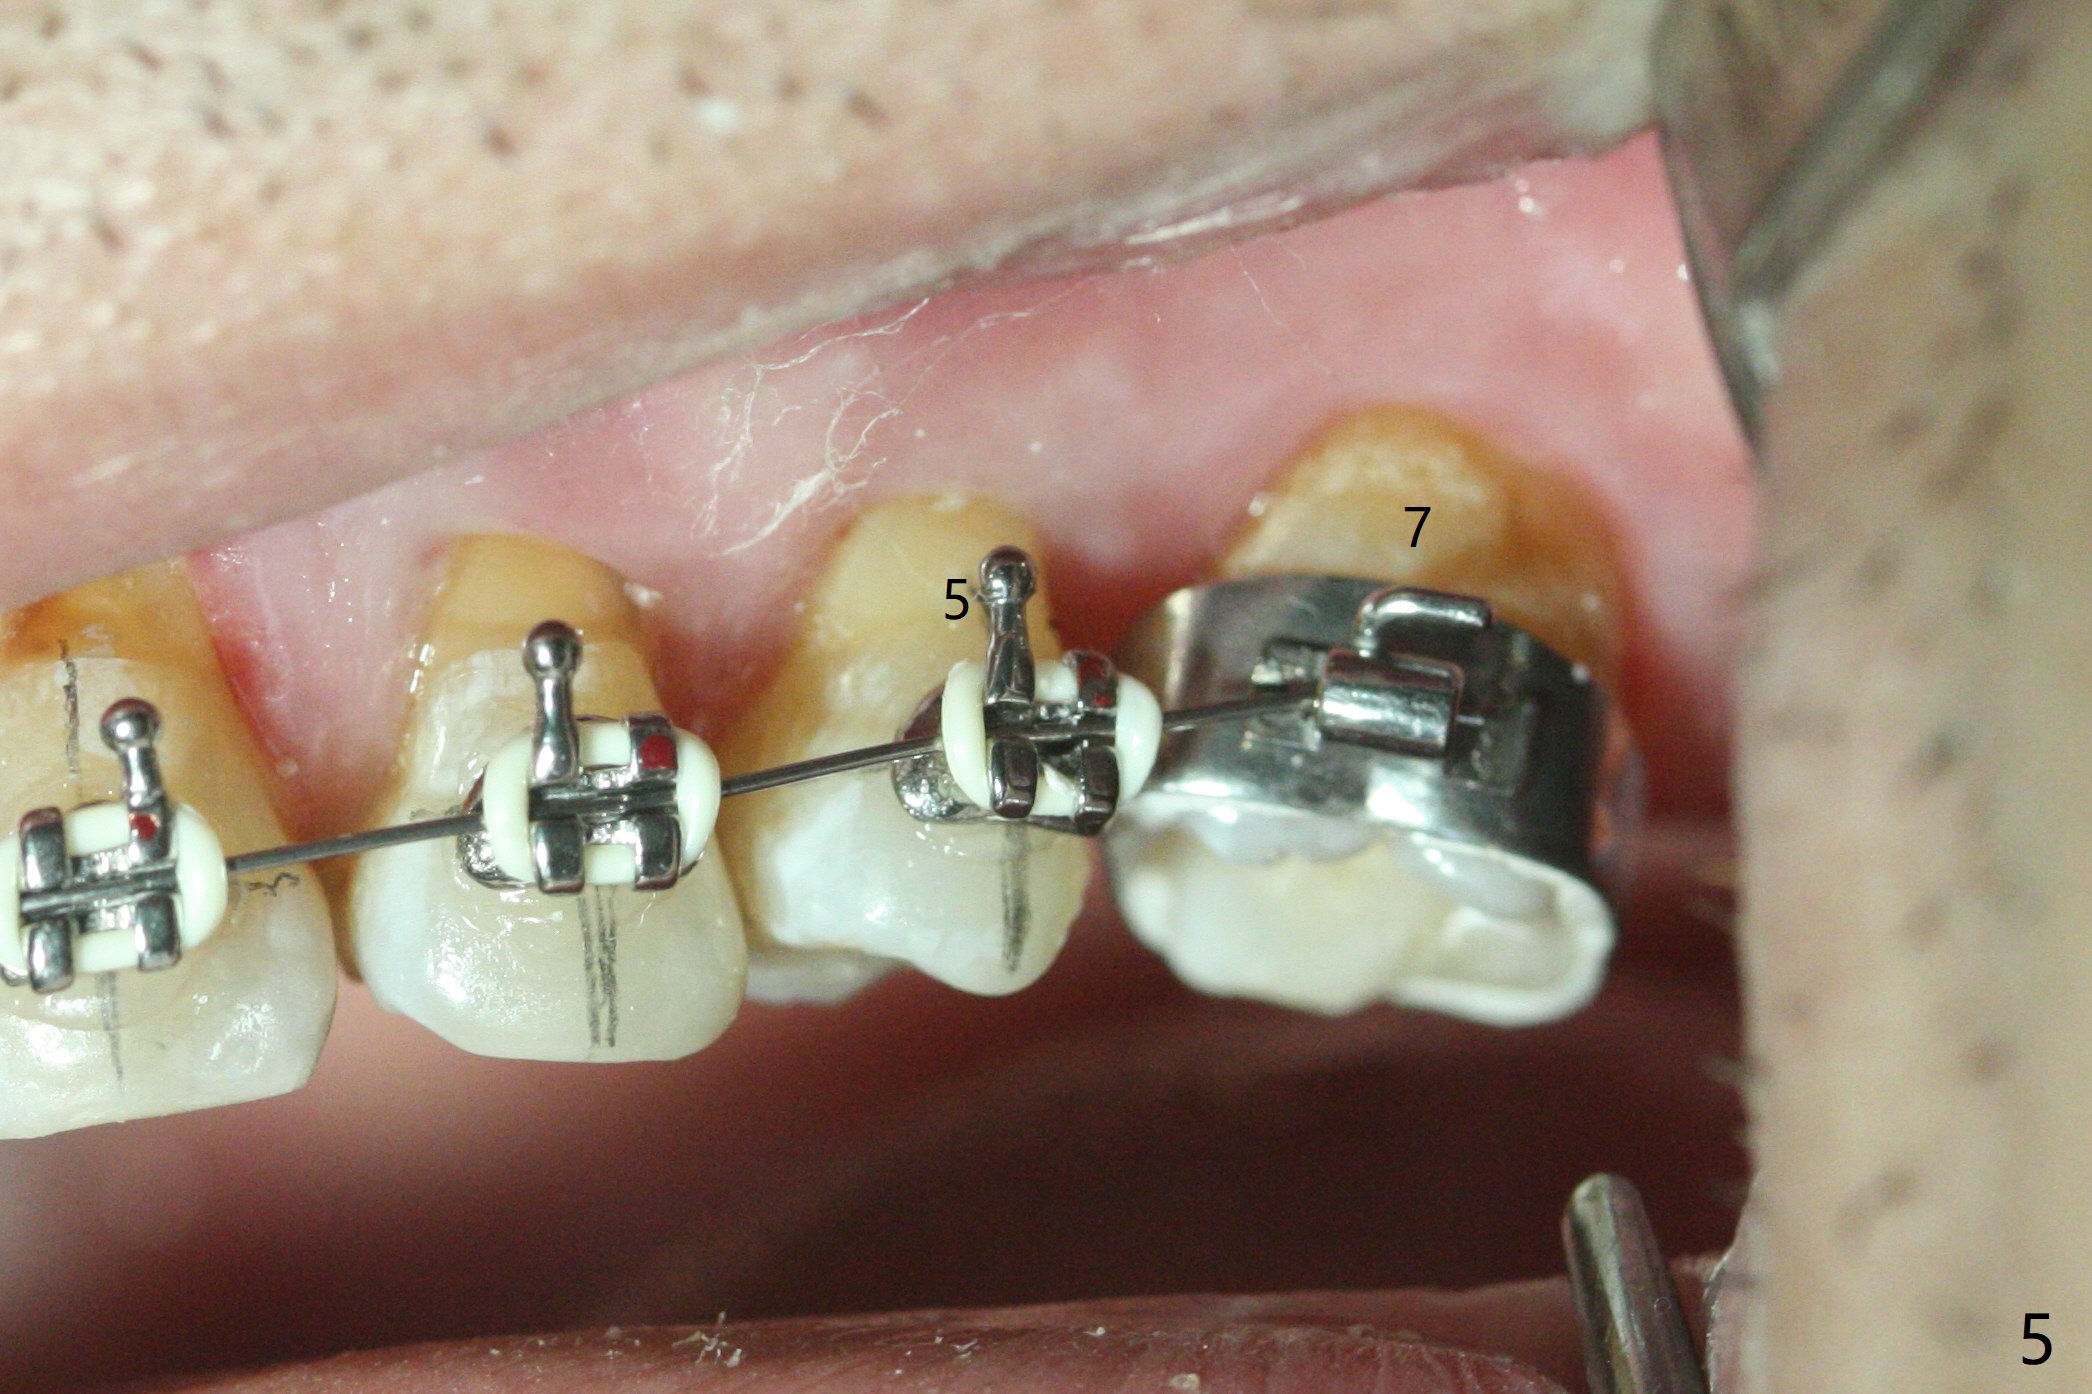

A 54-year-old man returns to office for UL7 upright 6 months post UR5 implant crown cementation (Fig.5,6). The ultimate purpose is to place implants at UL6 and LL 7. The latter will reduce severe occlusal wear especially in the lower anterior teeth (Fig.3,4). To solve the diastema between UR3 and 4 (Fig.1), the bracket at UR3 is placed in the height of contour (Fig.1 insert, Fig.4). Arch wire sequence may automatically close the diastema (Fig.1 insert arrows). In addition to tilting of UL7 (Fig.7), there are diastemata between U1s and UL3 and 4 (Fig.8,9 arrowheads). The patient is not tolerating orthodontic treatment well and requesting finishing the treatment early. We are considering mesializing UL7 instead of upright by placing a mini-implant between UL4 and 5 (Fig.10). There will be less interference of the roots of UL7 with the crown of the impacted UL8. There appears more space for a 1.6x8 mm mini-implant between UL4 and 5 (Fig.11) and UL 3 and 4 (Fig.12). Finally a mini implant is placed distal to UL7.